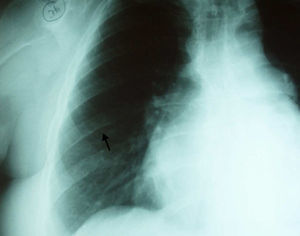

In order to exclude coronary artery disease (for surgical purposes) coronary angiography was also performed which revealed, once again, marked collateral circulation via the internal mammary artery and no coronary lesions (Figure 4). On retrospective review of the chest radiography, inferior rib notching was evident (Figure 5).